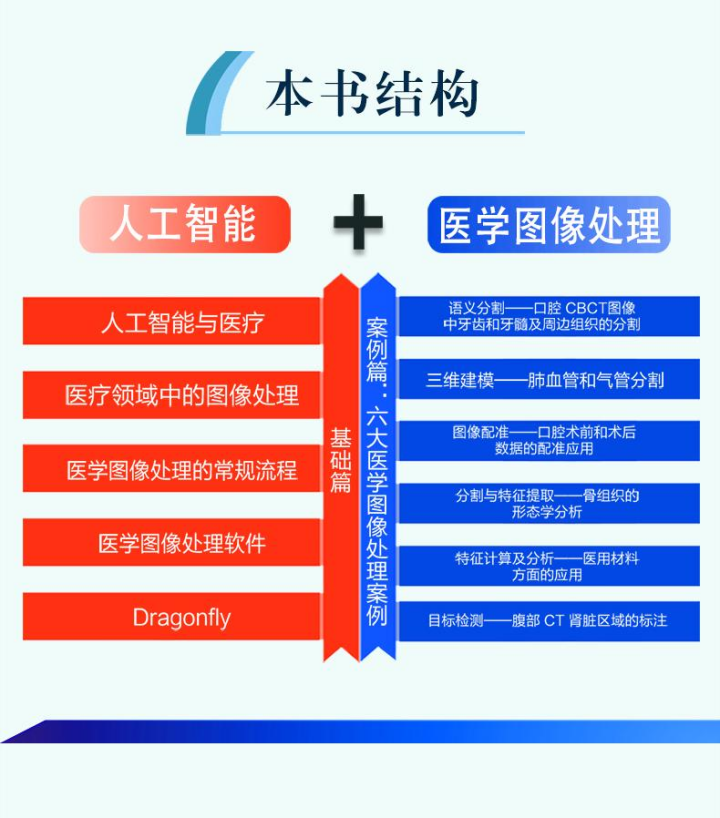

小异在看到这本书的时候发现:它的逻辑脉络十分清晰,不同于复杂高深的专业书,简单明了地分为基础理论和实战案例两大模块。

图:本书内容结构

第1部分讲解人工智能的基础知识:先从人工智能在医疗领域的发展讲起,普及一些背景知识,再过渡到医疗领域的图像处理技术,进而讲解医学图像的处理流程,最后介绍医学图像处理软件Dragonfly。

其中,前2章的科普将背景知识浓缩汇集,有助于读者快速通过了解行业、建立感性认知,节省了到处搜索的时间,可以将精力投入到专业技术学习中;后2章的知识可以让0经验读者大致了解医疗编程要点,做好医疗场景与技术知识的衔接。

考虑到 Python语言易上手的特点及其在人工智能领域的广泛应用,读者选用了三维图像专业处理软件 Dragonfly作为本书的软件工具,它是一款广泛应用于科研领域的图像处理软件,为用户提供了一个易使用且功能强大的人工智能应用平台,入手门槛较低。

第2部分深度剖析案例,涉及口腔医学、临床医学、材料学、工学等多个学科的交叉内容,是本书的重头戏。

通过 6 个真实的医学案例,展现人工智能技术在医学图像领域的应用,从医工交叉的角度出发,深入探讨了医学图像问题处理方法,旨在让读者了解如何将人工智能技术切实落地于医学图像学中,帮助相关从业者减少重复性工作,为医生和开发者两端搭建一座沟通的桥梁,进一步推广新技术和方法在该领域的应用。